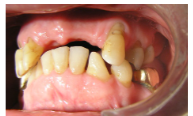

1) 1. Initial situation of teeth anterior and lateral view

2) Anterior view with denture